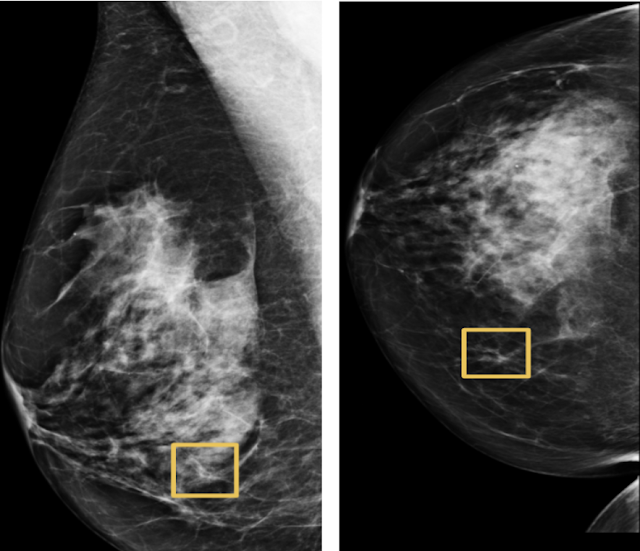

우리는 유방 조영술에 대한 딥러닝 모델이 의사가 유방암을 발견하는데 도움이 될 수 있음을 보여 주었습니다. 유방암은 평생 동안 미국 여성 8명 중 1명에게 1명에게 영향을 미치며 전문가보다 정확도가 높으며 위양성 및 위음성을 모두 줄입니다. 영국의 병원에서 비식별 처리된 데이터에 대해 훈련된 이 모델은 미국의 완전히 다른 의료 시스템에서 환자를 평가할 때 비슷한 정확도를 얻었습니다.

[그림5-머신 러닝으로 정확하게 식별하기 어려운 암 사례 예]